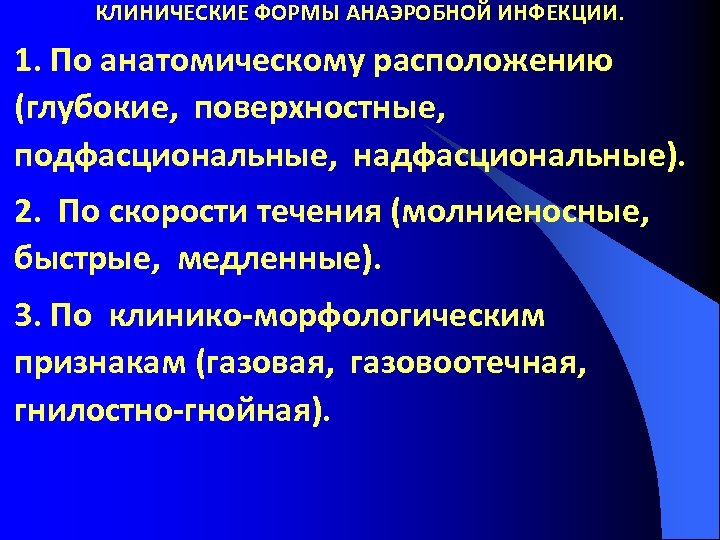

КЛИНИЧЕСКИЕ ФОРМЫ АНАЭРОБНОЙ ИНФЕКЦИИ. 1. По анатомическому расположению (глубокие, поверхностные, подфасциональные, надфасциональные). 2. По скорости течения (молниеносные, быстрые, медленные). 3. По клинико-морфологическим признакам (газовая, газовоотечная, гнилостно-гнойная).

КЛИНИЧЕСКИЕ ФОРМЫ АНАЭРОБНОЙ ИНФЕКЦИИ. 1. По анатомическому расположению (глубокие, поверхностные, подфасциональные, надфасциональные). 2. По скорости течения (молниеносные, быстрые, медленные). 3. По клинико-морфологическим признакам (газовая, газовоотечная, гнилостно-гнойная).